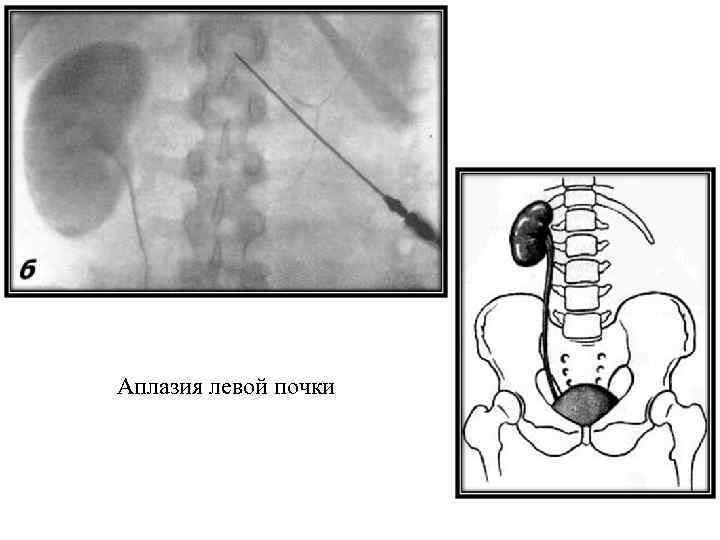

Аплазия левой почки

Аплазия левой почки